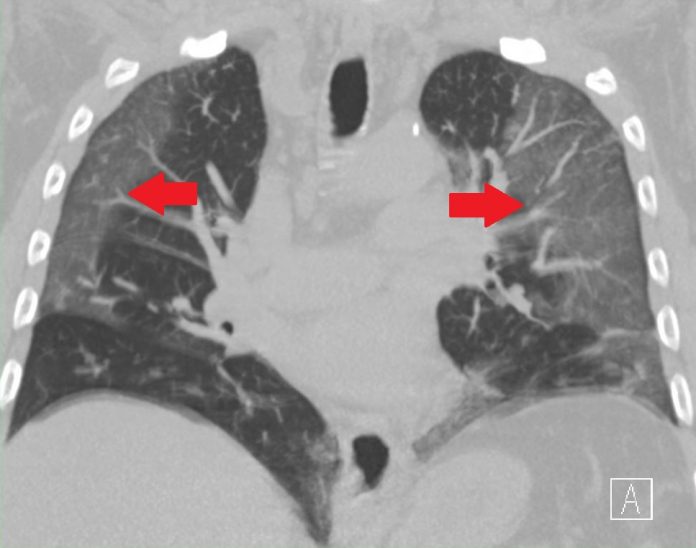

D’après de récentes observations de médecins aux Etats-Unis, en France et en Chine, le coronavirus provoque la formation de caillots de sang. Chez certains patients, comme l’acteur Nick Cordero, celle-ci a débouché sur une amputation d’un membre.

Les poumons ne sont pas les seuls à être attaqués, la maladie du Covid-19 a également la capacité de provoquer de tels caillots de sang dans les vaisseaux que les dégâts peuvent être considérables dans d’autres organes. Dans plusieurs services de réanimation, aux Etats-Unis notamment, les médecins ont observé plusieurs conséquences dramatiques de cette formation de caillots qu’on peut très difficilement déloger.

Cela finit parfois par asphyxier les membres. Ou, si les caillots de sang se forment dans les veines de la jambe, entraînant une phlébite, ils peuvent aussi se diriger vers les poumons, boucher l’artère et parvenir à les mettre à l’arrêt, ce qui provoque une embolie pulmonaire. Ce n’est pas tout, le coeur peut être attaqué et survient la crise cardiaque. Il arrive même aux caillots de remonter jusqu’au cerveau, et c’est l’accident vasculaire cérébral assuré.